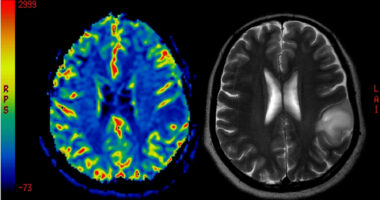

These symptoms occur due to inflammation in the brain and spinal cord, which damages the myelin sheath, a protective coating around nerve fibers that is essential for proper nerve communication. The specific symptoms that a person with MS experiences will depend on which parts of the nervous system are affected.